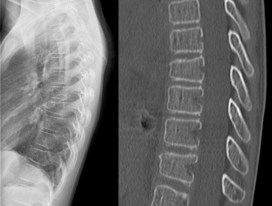

la fracture de Chance

synonyme : seat-belt fracture

le mécanisme est typiquement un étirement du rachis avec le bassin bloqué par la ceinture de sécurité pelvienne (sans baudrier). C’est une fracture hautement instable avec risque de déplacement secondaire, qui nécessite une fusion chirurgicale. il s’agit d’un abord postérieur avec ligature ou instrumentation courte et immobilisation par corset.